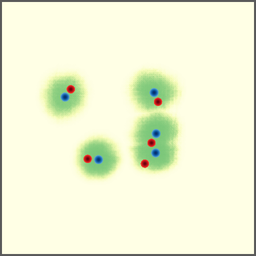

Shift-Invariant Tracking. The POINT network benefits from the shift invariant property of the convolution operation, which makes it less sensitive to the in-plane offset of the DRRs. Figure 8 shows some tracking results from the POINT network. Here the odd rows show the (a) X-ray and (b-d) DRR images. The heatmap below each DRR shows the tracking result between this DRR and the leftmost X-ray image. The red and the blue marks on the X-ray and DRR images denote the POIs. The red and the blue marks on the heatmaps are the ground truth POIs and the tracked POIs, respectively. The green blobs are the heatmap responses and they are used to generate the tracked POIs (blue) according to Equation (7). The numbers under each DRR denote the mPD scores before and after the tracking. As we can observe that the tracking results are consistently good, no matter how much initial offset there is between the DRR and the X-ray image. This shows that our POINT network indeed benefits from the POI convolution layer and provide more consistent outputs regardless of the in-plane offsets.

Refer to caption

(a)

(b) 13.6 \rightarrow 7.3

(c) 22.9 \rightarrow 9.0

(d) 37.1 \rightarrow 7.8

(e)

(f) 19.5 \rightarrow 8.7

(g) 26.0 \rightarrow 9.5

(h) 41.1 \rightarrow 11.4

(b)

(c)

(d)

Figure 8: POI tracking results. (a) X-ray image. (b-d) DRR images with different in-plane offsets. The heatmaps of the tracking results are all aligned with the X-ray images and appear similar, showing the shift-invariant property.